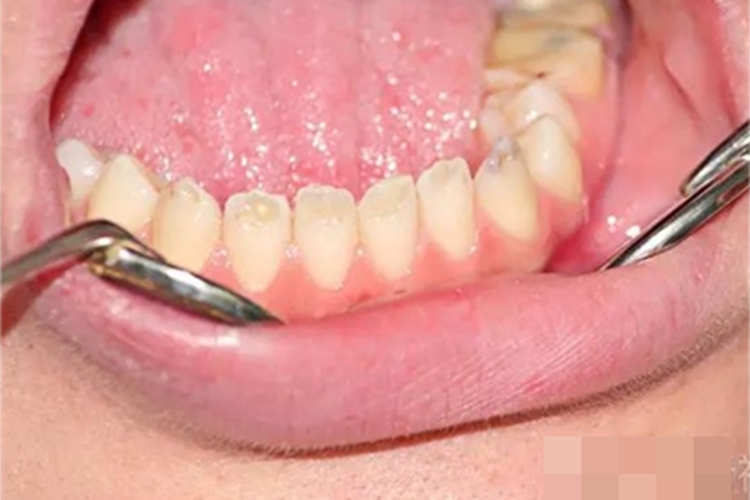

牙釉质发育不全患者的牙齿会出现色泽和透明度改变,表面出现白垩色釉质,同时牙齿顶端变透明、变薄,但患者可能无敏感、疼痛等自觉症状。

牙釉质发育不全者应预防龋病的发生。对于牙着色或缺陷,可使用复合树脂、烤瓷冠等方法进行修复治疗。需注意的是,以上治疗均需在医生指导下进行。